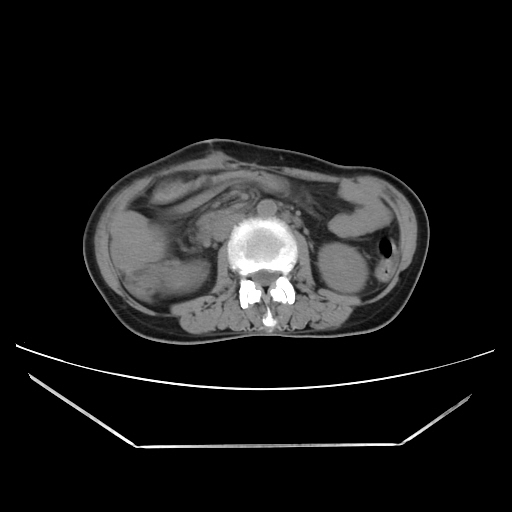

Radiological images:

CT-Scan investigation done on 16Apr16